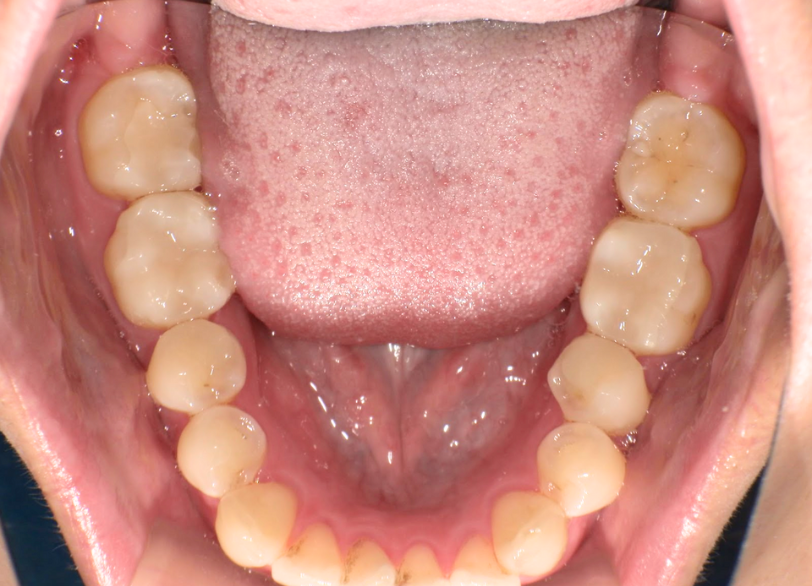

矯正治療、かみ合わせの治療 2019.07.17矯正歯科治療の症例 矯正治療、かみ合わせの治療の治療例です。費用:40万治療期間:1.5年リスク説明:元々顎関節症などの顎の疾患がある場合には治療期間が延びることがあります。後戻りを避けるため固定をしないといけない場合があ... 続きを読む